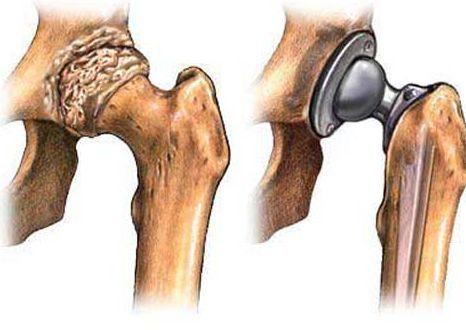

5、外科手术

网络配图

如果保守治疗不起作用,你可能需要考虑骨头重整、关节置换的手术了,一般来讲,外科手术的风险包括感染和血栓。另外,人工关节也可能会磨损或脱落,最终可能需要更换。